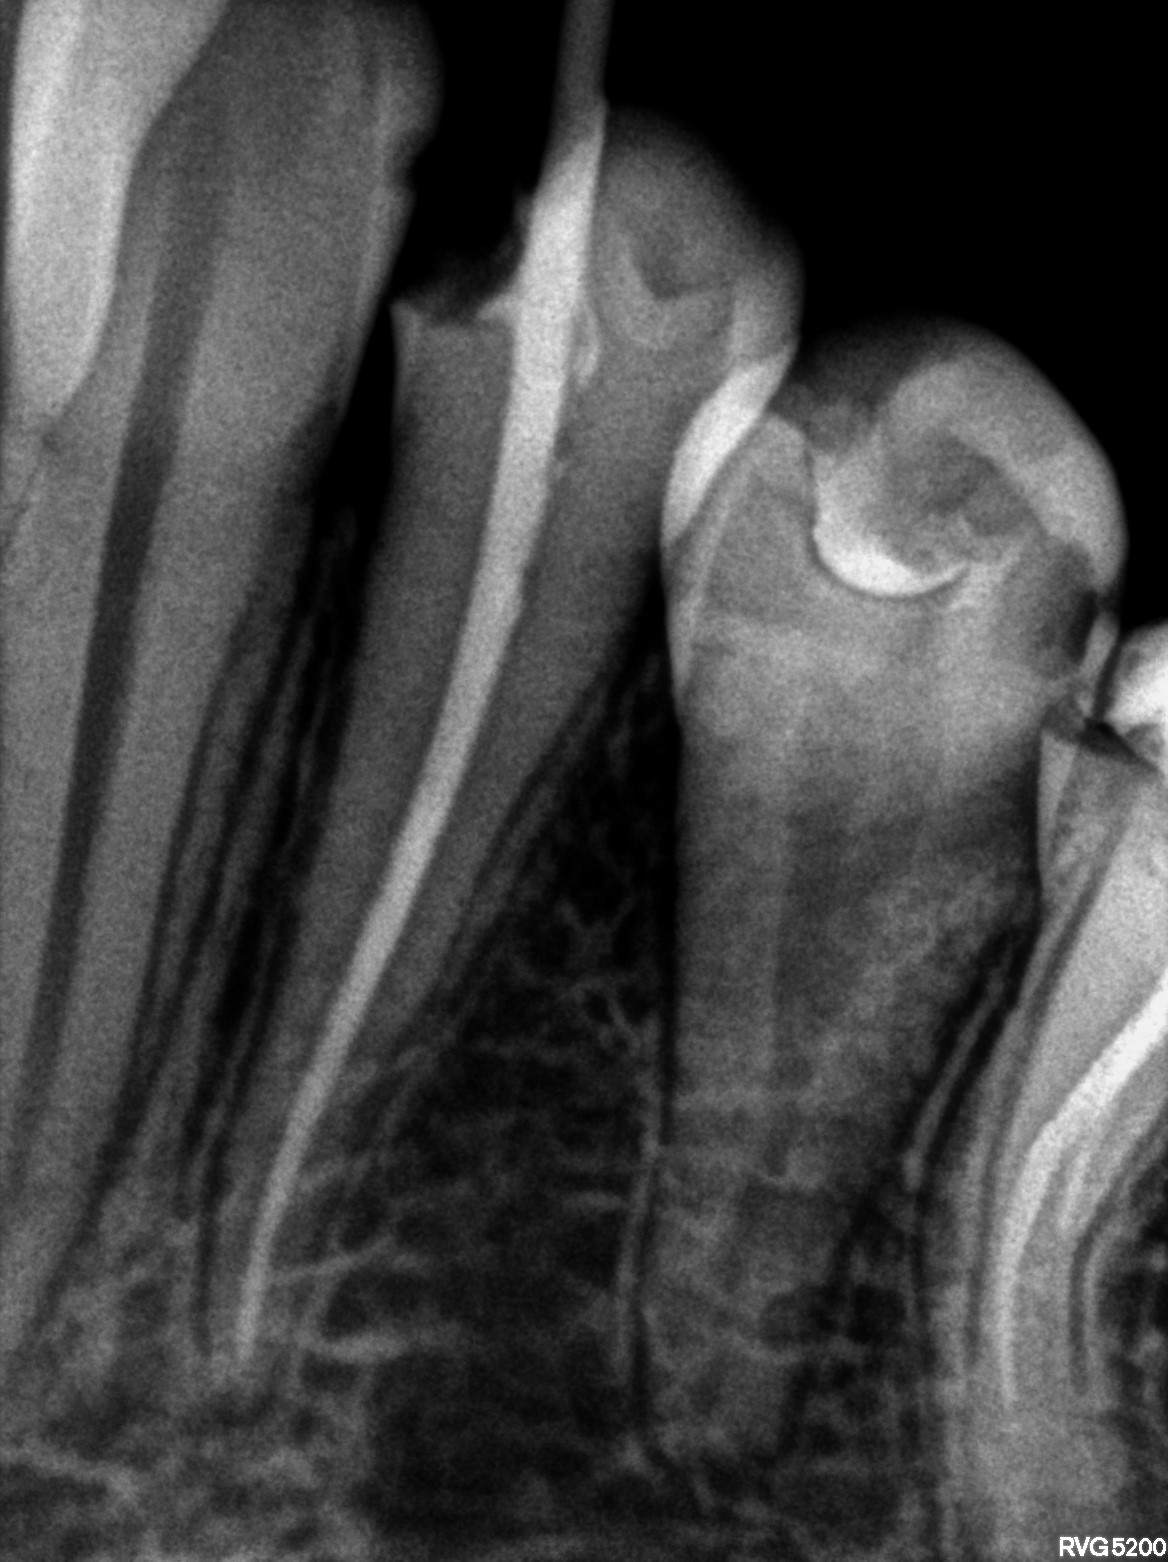

Dental Radiographs FHIR: DocumentReference · LOINC 24641-7

R55.jpg

24641-7

R60.jpg

R61.jpg

R59.jpg

R56.jpg